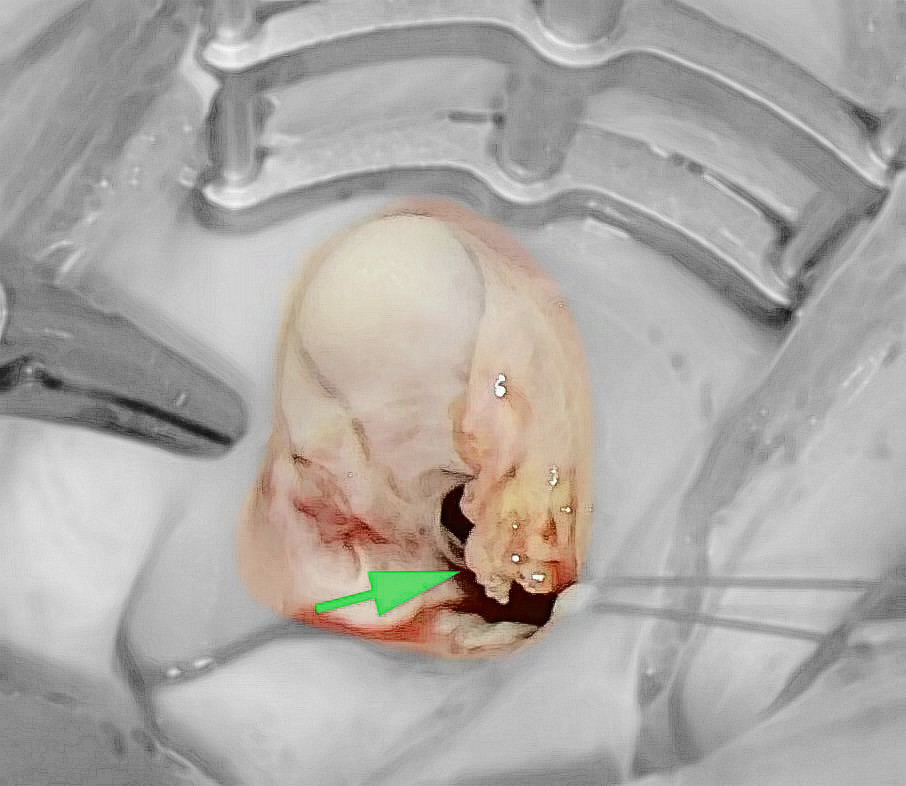

手术过程中

后来,少女患者及家属来到我科,再次复查彩超时,发现二尖瓣上有多个赘生物,最大的达1.5cmX1cm,同时合并前瓣的穿孔,瓣膜重度返流,在继续使用抗生素的情况下,使用胸腔镜做了微创的心脏瓣膜修复手术。术后再没听到心脏杂音,复查心脏彩超也没再见到瓣膜的返流,康复后即可恢复到正常的生活状态。